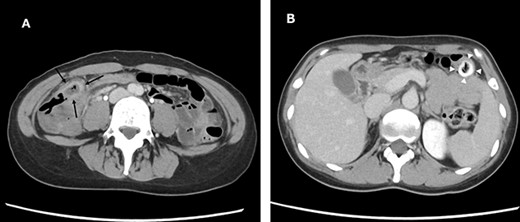

A 38-year-old woman presented with lower right abdominal pain of 3 days duration before the consultation. She had a history of left ovarian cystectomy and no history of medication use or allergies. She was 172-cm tall and weighed 59.0 kg. On examination, there was right lower abdominal pain with no rebound tenderness. The white blood cell count was 13 600 /μl, and the C-reactive protein was 3.8 mg/dl. Contrast-enhanced computed tomography (CT) revealed a 4-cm cecal diverticulum with inflammation and a fecalith (Fig. 1). An abscess penetrated through the mesenteric side and was localized in the mesentery. The diagnosis was cecal colonic diverticulitis and classified as Hinchey II. The abdominal symptoms were localized; hence, the patient was treated with antibiotics. From Day 1 of hospitalization, she was on nil per oral and administered CMZ at 3 g/day. On hospitalization Day 3, the right lower abdominal pain improved, and contrast-enhanced CT imaging was performed. The cecal colonic diverticulitis improved, and the fecaliths migrated to the transverse colon (Fig. 2). Moreover, the inflammatory reaction improved. In a multidisciplinary meeting, we discussed that the patient should undergo a detailed examination, including colonoscopy, and elective surgery after readmission. However, we suggested that surgical treatment should be performed as early as possible after considering the risk of early recurrence and bleeding. The patient wished to undergo minimally invasive surgery; thus, we performed an immediate ileocolectomy and lymphadenectomy using SILS as we did not rule out the likelihood of malignant disease.

Abdominal and pelvic CT with intravenous contrast at the time of consultation. Axial image (A) demonstrated cecal colon diverticulum (black arrows) and sagittal image (B) demonstrated thickening and mural edema of the diverticulum (white arrowheads), indicating inflammation.